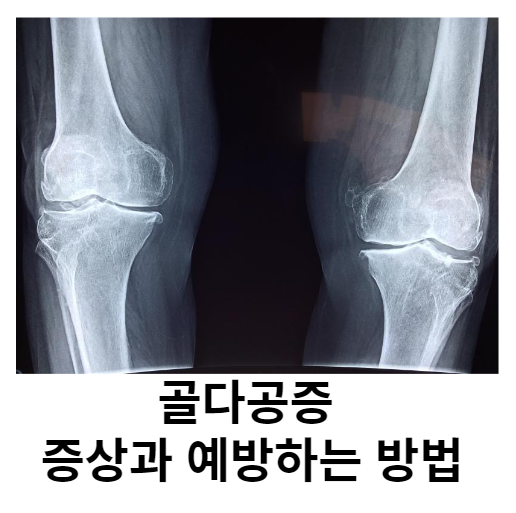

균형잡힌 식습관이 건강에 중요하다는 사실은 누구도 모르는 것 같아요. 건강관리에도 활용하고 있는데 칼슘, 마그네슘, 비타민D로 구성된 칼마디는 뼈 건강 유지는 물론 근육, 건강 관리에도 도움을 주는 것으로 알려져 있습니다. 오늘은 골다공증 원인과 예방법에 대해 이야기나누도록 하겠습니다.

골다공증 원인

골밀도는 일반적으로 나이가 들수록 감소하고 여성의 경우 폐경기에 접어들면서 호르몬 변화가 발생하지만 일반적으로 골밀도는 시간이 지남에 따라 점차적으로 감소합니다. 또한, 골다공증을 일으키는 질병이나 약물도 골다공증을 유발할 수 있으며, 뼈의 구성성분인 칼슘과 흡수를 돕는 비타민D가 부족할 경우 골다공증에 더 취약할 수 있습니다.

골다공증 증상

대부분의 경우 증상은 없으나 쉽게 골절이 발생할 수 있으며, 골절이 일어나기 전까지는 이상을 인지하지 못하는 경우도 많습니다. 골절 후 회복은 느리고 오랜 시간이 걸리기 때문에 조기 진단과 예방이 중요하며, 뼈 건강을 유지하기 위해서는 필요한 영양 섭취와 규칙적인 운동이 권장됩니다.

골다공증 예방하는 방법

낮은 골밀도를 강화하고, 골절 위험을 낮추며, 통증을 관리하는 것이 중요합니다. 규칙적인 운동을 통해 뼈를 강화하고 균형 감각을 향상시키며, 넘어지지 않도록 실내 환경을 개선하는 것도 골절 예방에 도움이 될 수 있습니다. 식단에 칼슘, 비타민 D, 마그네슘을 충분히 섭취하세요. 하지만 매일 식사에 포함시키기 어려울 수 있으므로 칼마디 영양제를 섭취하는 것도 권장됩니다.